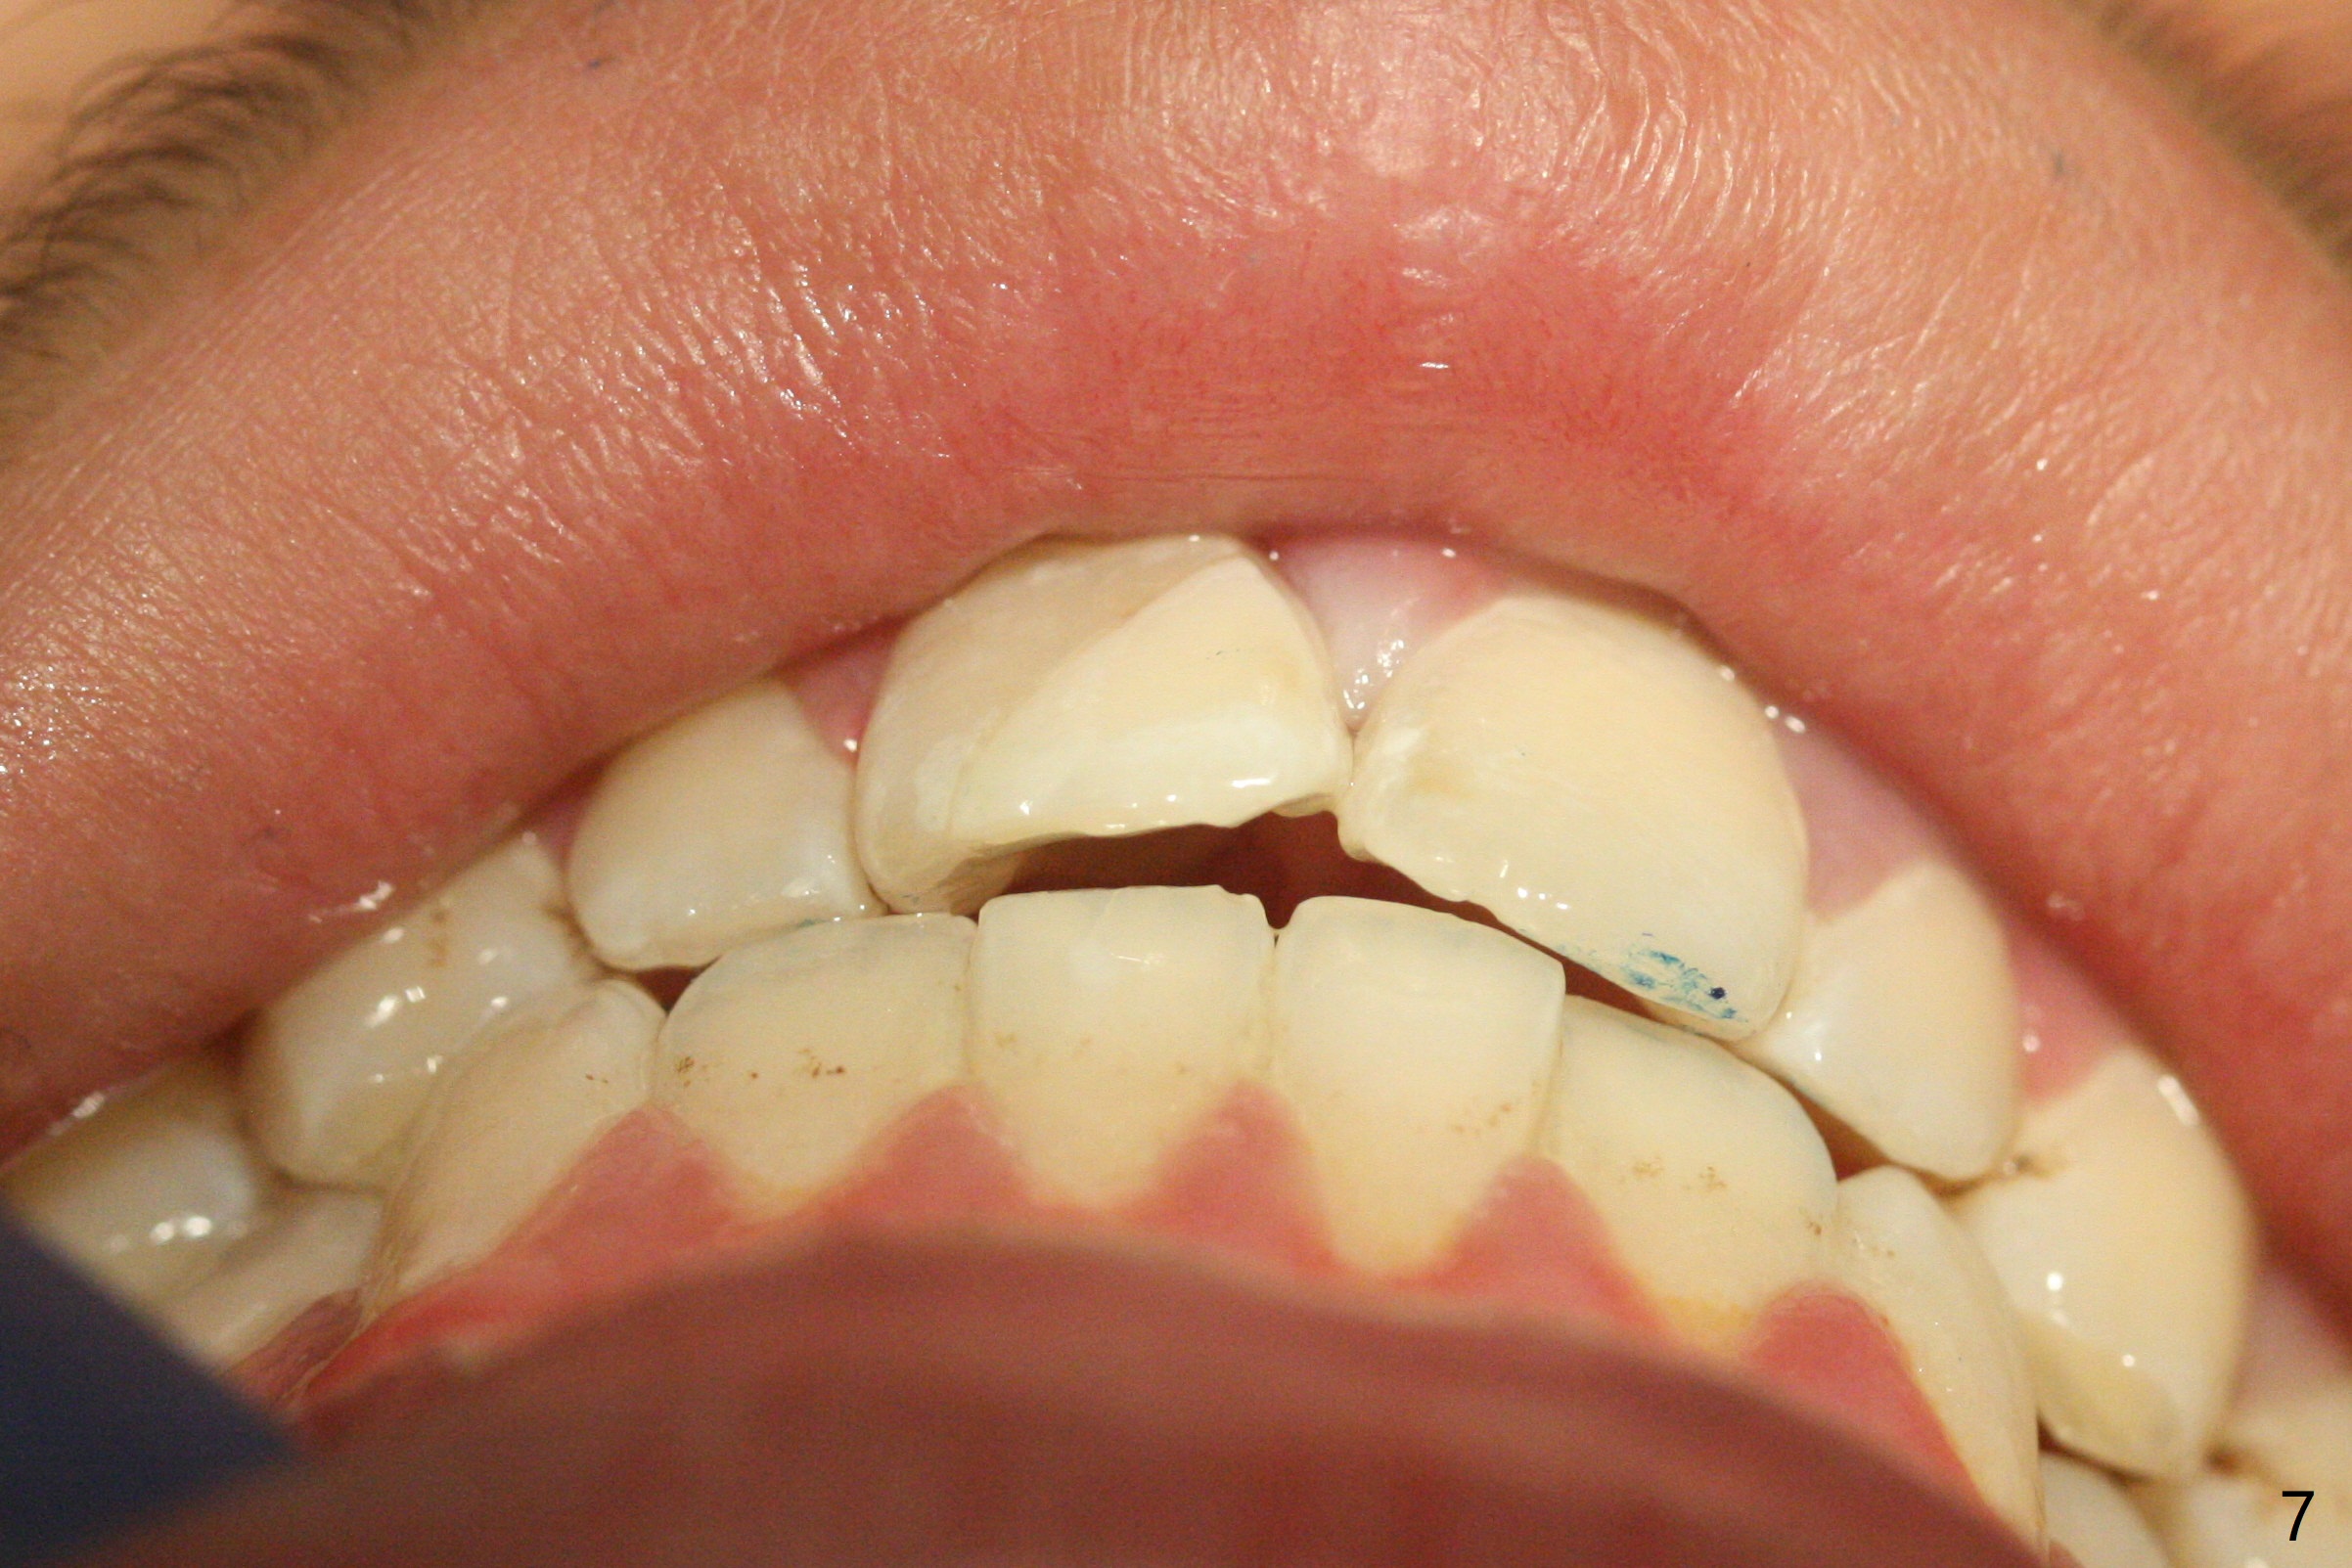

A 16-year-old man fractured the tooth #8 yesterday (Fig.1) with pulpal exposure (Fig.2) and slightly subgingival (Fig.3 <). With 2 gingival retraction cords, rubber dam and floss, the mesial margin is exposed (Fig.4). The mesial pulpal horn is increased slightly with a 330 bur with minimal pulpotomy. MTA is applied (Fig.5 <). A curette is placed over the MTA for hemostasis while it is setting. RelyX Ultimate Adhesive Resin Cement bonding is used to reattach the fracture fragment in place (Fig.6,7). Pulpal vitality will be monitored. A crown will be placed if the tooth discolors due to MTA and the pulp remains vital. Mineral trioxide aggregate (MTA), composed mainly of tricalcic silicate, tricalcic alluminate, bismuth oxide, is a particular endodontic cement. It is made of hydrophilic fine particles that harden in the presence of dampness or blood. The re-attached tooth remains asymptomatic 9 days postop (Fig.8) when he returns for prophy.

16岁男孩,昨天右上中切牙撞击电脑发生折裂(图一),近中牙髓角暴露(图二),裂缘稍微龈下(图三 <),使用两个牙龈牵拉线,橡皮障和牙线,近中折裂边缘暴露(图四)。你会如何处理?使用330钻头稍微扩大髓角开口,去除少量牙髓,填入微量MTA (图五<),希望形成新的牙本质,关闭开口,维持牙髓活性。出血控制后,应用树脂粘合剂将断片固定于原位(图五,六,七)。术后9天牙齿无症状(图八),病人回来洗牙。